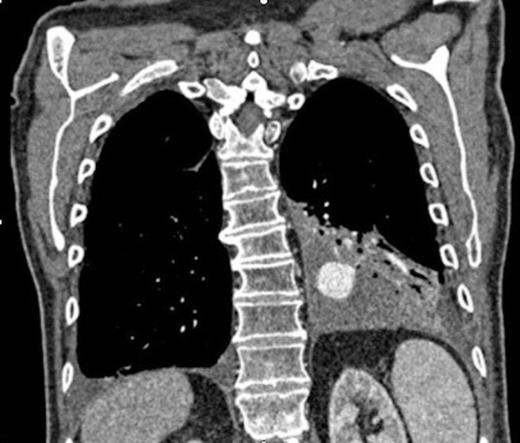

Selective digital subtraction angiography image of left lower lobe pulmonary artery, demonstrating filling of the inflammatory aneurysm and depicting the feeding branches clearly

Digital subtraction angiography post deployment of the AVP 4 device in the PA branch feeding the aneurysm (arrow). No residual or collateral filling seen